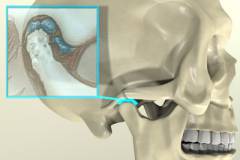

Височно-нижнечелюстной сустав (ВНЧС) — парный орган, расположенный на стыке нижней челюсти и височной кости черепа. Это комбинированный сустав, обеспечивающий синхронные движения обеих челюстей. Его основная функция — подвижность нижней челюсти.

- Суставные поверхности. Сустав образован суставной головкой нижней челюсти и нижнечелюстной ямкой височной кости.

- Внутрисуставной диск (хрящ). Волокнистый хрящ между суставными поверхностями делит полость сустава на верхний и нижний отделы.

- Связочный аппарат. В области ВНЧС выделяют одну боковую и две меньшие связки, ограничивающие движения суставной головки. Боковая связка предотвращает смещение назад, а малые поддерживают нижнюю челюсть. Сустав также соединен с молоточком среднего уха двумя связками.